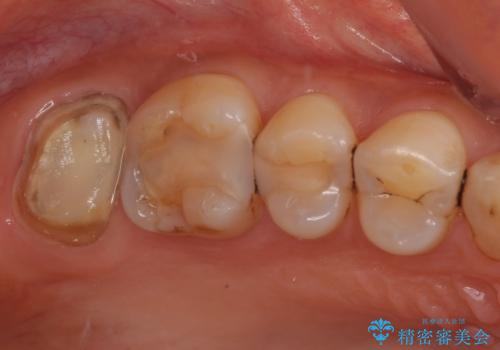

- 奥歯の被せものが欠けたとのことで来院された患者様です。上の奥歯なので機能面や強度を優先しPGAクラウン(ゴールドクラウン)のご提案をしましたが、セラミックの被せものがよいとのことでオールセラミッククラウンによる補綴治療を行っていくことにしました。

拡大鏡視野下で古い被せものを除去し、オールセラミッククラウンに適した形に整えました。